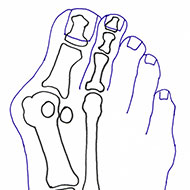

Lo schema mostra che l’alluce è deviato lateralmente (valgo). Colpisce maggiormente la “cipolla” costituita dalla sporgenza sotto la pelle della testa del 1° metatarsale; urta contro la scarpa e causa infiammazione e dolore.

- 1. ALLUCE VALGO = spostamento laterale dell’alluce;

- 2. METATARSO VARO = spostamento verso l’interno del 1° metatarso.

Nella foto si vede un alluce valgo deformato (ROSSO) e un alluce operato tre anni fa con la tecnica del dott. Scala (VERDE). L’immagine mostra l’allineamento delle ossa del piede. L’alluce è bello dritto e non si sposta più.